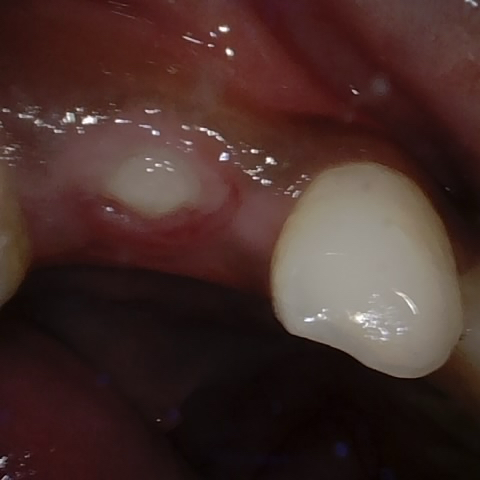

Annotated as "Good"